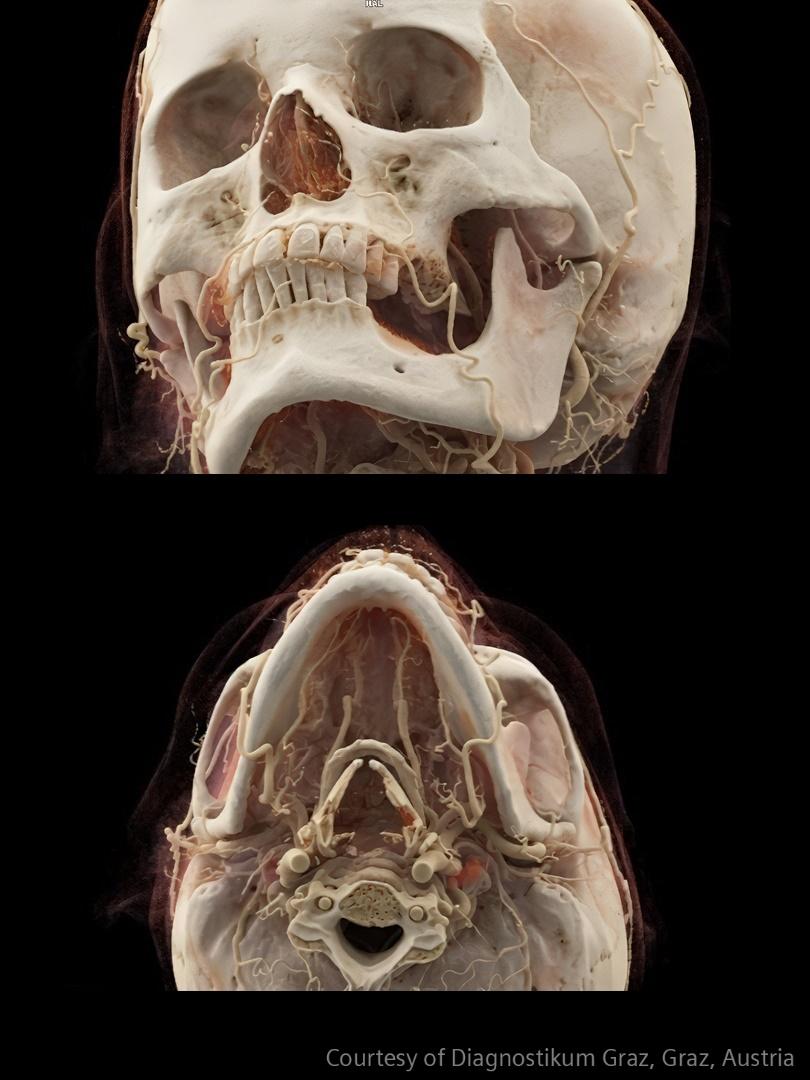

In stroke care, time is brain. Rapid and accurate imaging is crucial to assess the extent of brain injury and guide immediate treatment. Angiography, MRI, CT, ultrasound, and lab diagnostics are essential tools in identifying stroke type, location, and severity. Advances in imaging technology now allow for even faster acquisition, improved resolution, and enhanced visualization of brain tissue and blood vessels. Innovations such as perfusion imaging, real-time vascular mapping, and AI-assisted diagnostics are transforming stroke workflows and enabling precise, timely interventions.